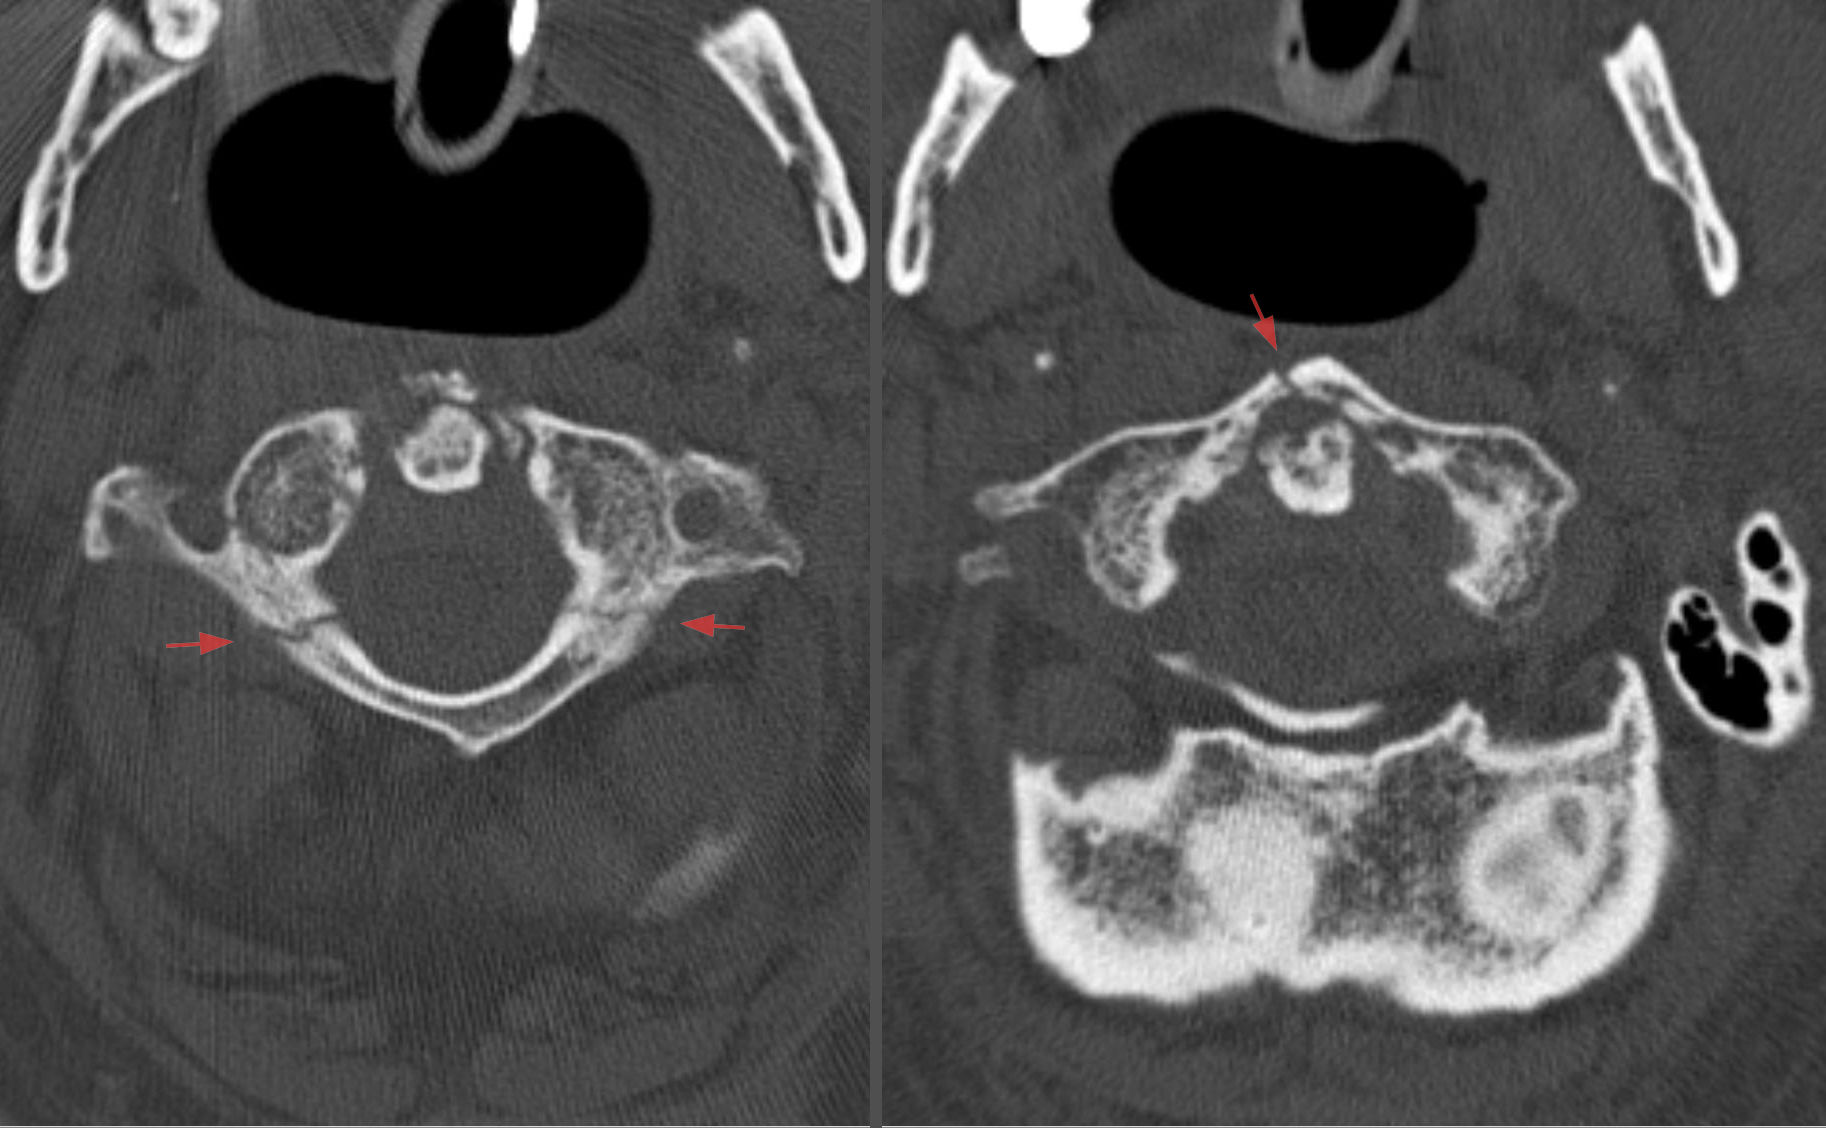

CIR - fratura do enforcado: fisiopatogenia, local de fratura, prognóstico

hiperextensão aguda coluna: dente do áxis na pars interarticulares

bom prognóstico

CIR - fratura de jefferson: local

ruptura do anel do atlas